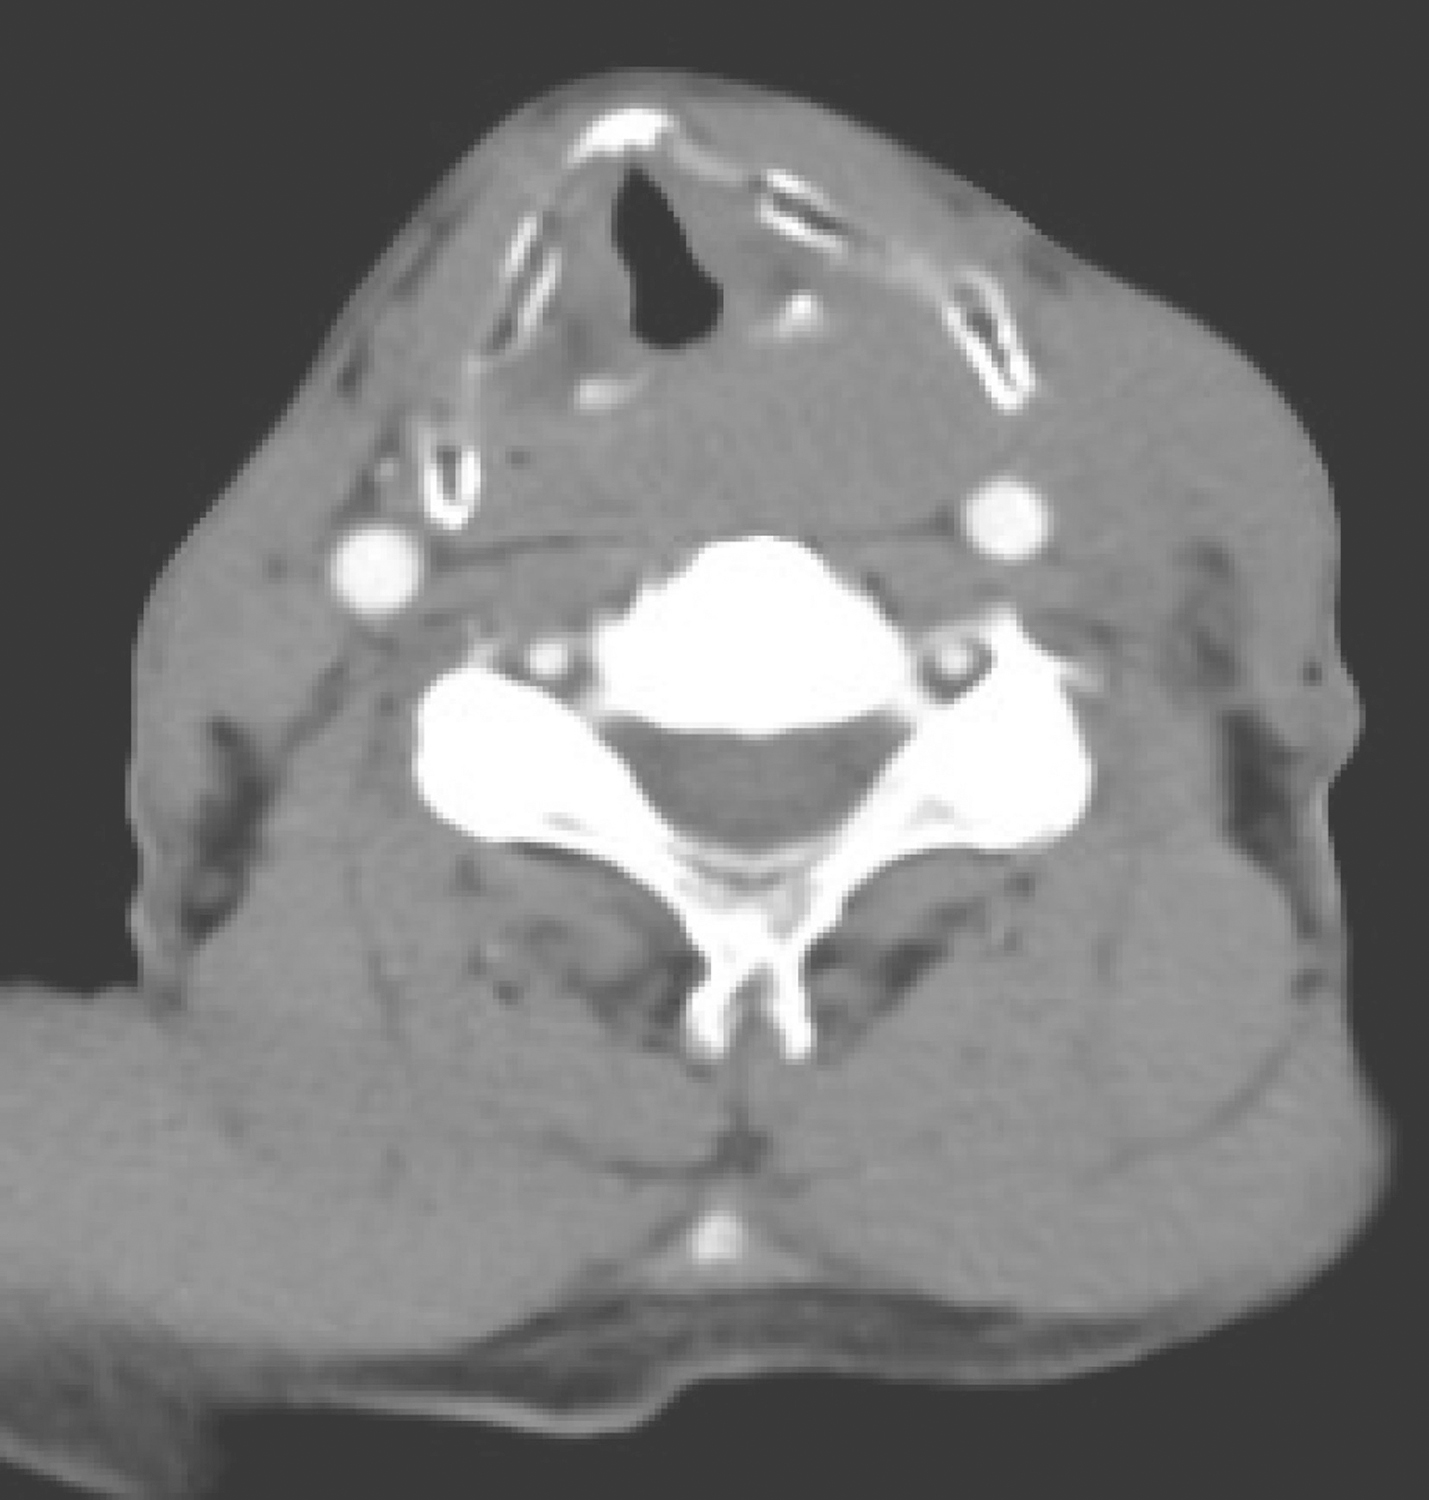

1小时条评论53岁男性,多年吸烟饮酒,因咽痛1个月于2008年4月29日收入头颈外科。如何诊治? 【病例简介】 患者男性,53岁。因咽痛1个月于2008年4月29日收入头颈外科。1个月前患者无明显诱因出现咽部疼痛,呈持续性,吞咽时加重。无发热、咳血等,在当地医院检查示左侧磨...